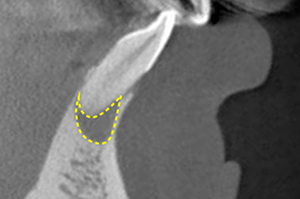

Bacteria that have reached the pulp will travel through the root canal, the cavity where the pulp used to be, to the the root apex, and finally proliferate in the bone that supports the tooth (Fig. 8).

This is called a "periapical lesion" (Fig. 9), and when this occurs, the tooth begins to move easily.